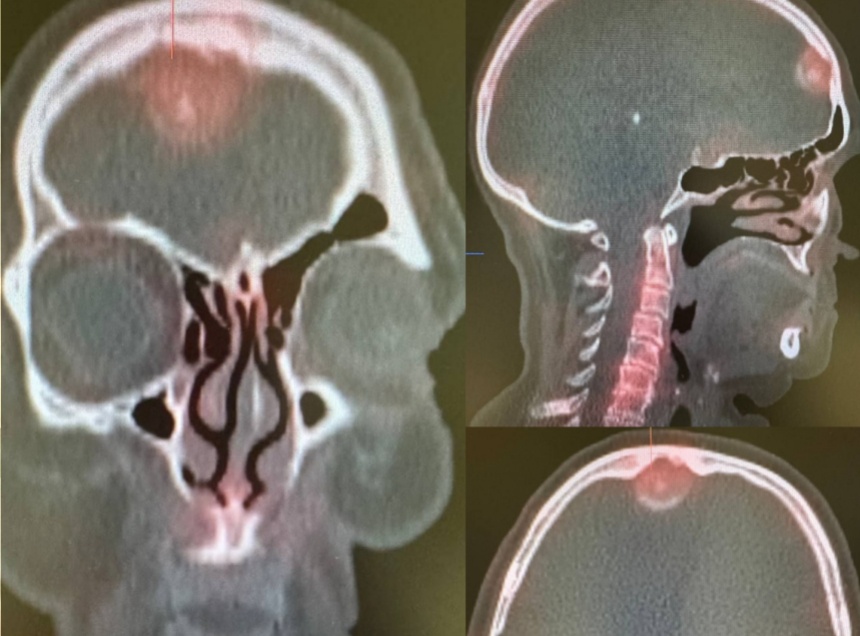

Симптомы, особенно жалобы на боли в костях, могли указывать на метастазы. Онколог назначил пациентке дополнительное обследование, включающее сцинтиграфию. Благодаря этому и пациентки выявили очаг гиперфиксации радиофармацевтического индикатора в лобной области.

В ходе дальнейших исследований в лобной области головного мозга обнаружили новообразование – менингиому. Она оказывала давление на окружающие ткани и могла вызывать описанные пациенткой симптомы. Пациентку успешно прооперировали. В ходе операции радикально удалили опухоль, что улучшило состояние женщины.